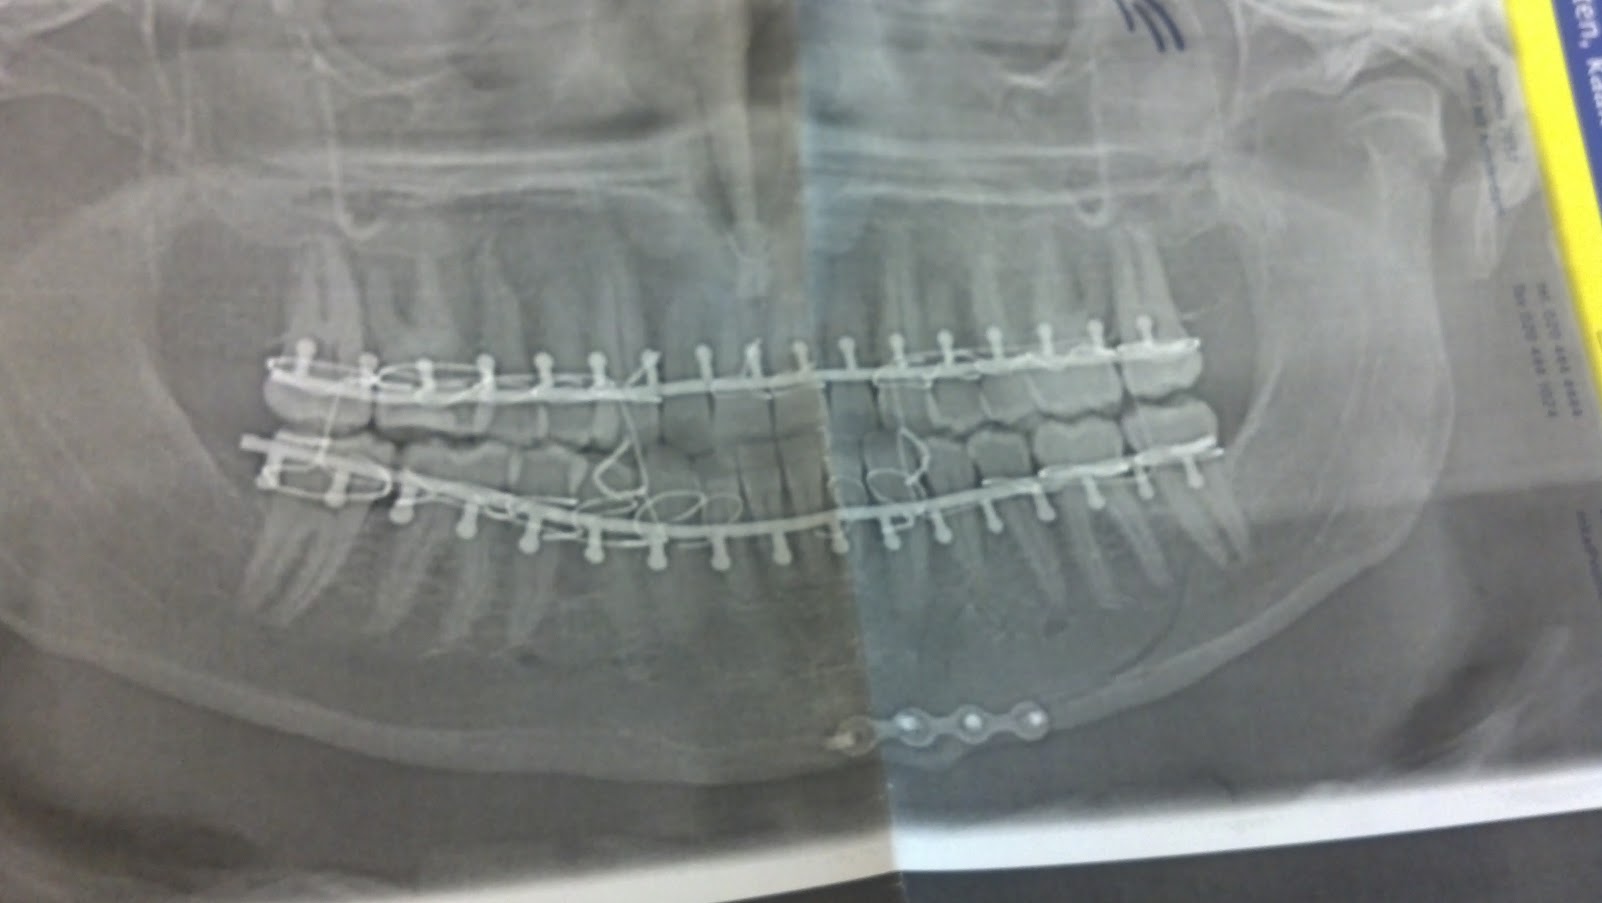

I broke my jaw on the 4th day after moving to the Netherlands